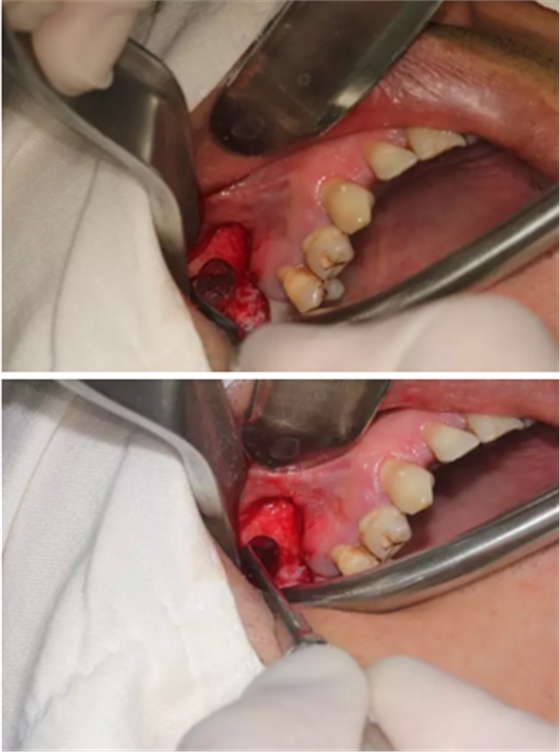

【病例分享】上頜竇大囊腫外提升